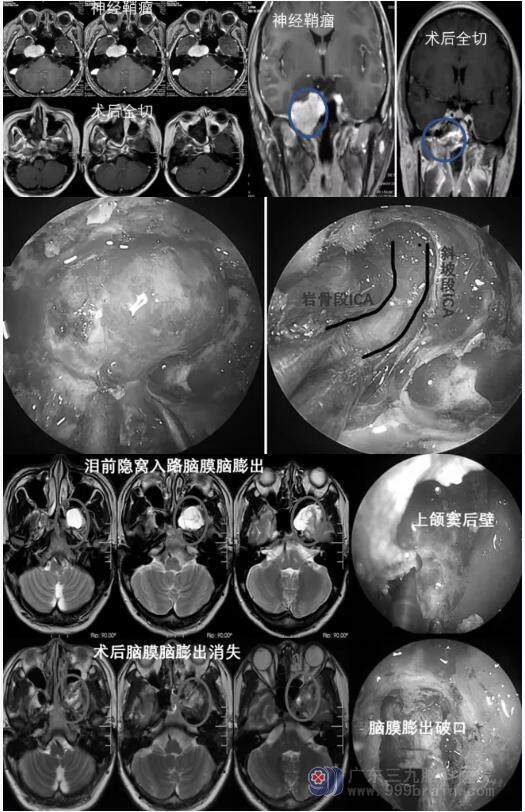

颅咽管瘤

开颅手术还是在神经内镜下经鼻入路,究竟哪种方式更能实现颅咽管瘤的更大切除程度?目前仍有很大争议。从临床上而言,神经内镜下扩大经鼻入路适用于位于鞍上中线和视交叉后的颅咽管瘤,在选择适应证的切除分级、可视化和功能保留方面有显著优势;传统开颅更适用于治疗远离中线的肿瘤;对于特殊的病例有时候需要两种治疗方式联合使用。总的来说,选择哪种手术方案,这取决于疾病的特点以及手术者的熟练程度。

侧颅底病变

神经内镜下扩大经鼻入路的技术应用于侧颅底病变,能够通过利用鼻腔解剖自然腔隙,由前至后的内镜路径,能够近距离观察,并具有广角放大、术中视野高清的特点,能够充分增加暴露空间;双鼻腔显微操作及精细内镜器械配合,保障了手术自由度。